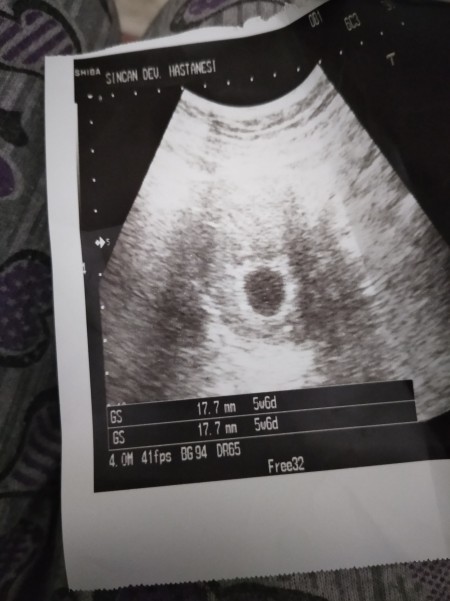

Hamilelikte boş kese kaçıncı haftada belli olur. öte yandan kesenin ultrasondaki görüntüsü de bu iki durumun ayrımında yol gösterici olabilir. Boş gebelik ile çok erken dönemdeki normal bir gebeliği ayırdetmenin en önemli yolu kese içinde yolk kesesi adı verilen yapının izlenmesidir. Haftasında ise artık embriyo ve kalp atışının görülebilmesi gerekmektedir. Hafta olmasına rağmen kese içinde bebek görülmüyorsa boş gebelik tanısı konabilir.

Son adet tarihinden itibaren 5 hafta geçtikten sonra ultrason ile boş gebelik ya da normal gebelik teşhisi yapılabilir. Boş gebelik ile çok erken dönemdeki normal bir gebeliği ayırdetmenin en önemli yolu kese içinde yolk kesesi adı verilen yapının izlenmesidir. öte yandan kesenin ultrasondaki görüntüsü de bu iki durumun ayrımında yol gösterici olabilir. Daha erken fark edilirse düşüğün gerçekleşmesi beklenmez hekim tarafından erken müdahale ile boş gebelik sonlandırılır.

Boş gebelikte de hormonlar üretildiğinden dolayı hamilelik testlerinde pozitif sonuç alınır. Ultrason ile boş gebelik kaçıncı haftada belli olur sorusunun cevabı olarak normal gebeliklerde fetusun ultrasonda görüldüğü haftaları verebiliriz. Boş gebelik ile erken gebelik belirtileri birbiri ile aynıdır. Gebelik kesesi en erken 4 5 5 haftalık gebelik olduğunda transvajinal ultrason ile görülebilir kanda gebelik beta hcg değeri 3000 4000 düzeylerine vardığında yani 6 haftalık gebelik olduğunda gebelik kesesi karından ultrason ile izlenebilir.

Kadınlarda kese ve plasenta oluşumu varken içerisinde embriyo oluşmaması durumunda oluşan boş gebelik birçok kadının doktora gidene kadar. Sağlıklı bir hamilelikte gebelik kesesi vajinal ultrason ile 4 4 5 hafta karından ultrason ile en geç 5.